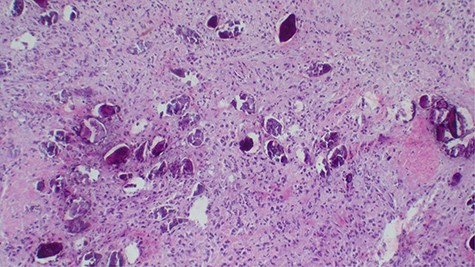

Laboratory investigations revealed a low platelet level of 53 per microliter and hemoglobin level of 10.7 g/dl. Renal profile, white blood count and serum electrolytes were within normal range. Computed tomography intravenous urogram revealed a large heterogeneous mass, measuring 5.5 × 4.5 cm at the right superolateral aspect of the urinary bladder with ipsilateral hydronephrosis and hydroureter. Bone scan study was unremarkable. Urothelial cell carcinoma of the urinary bladder was clinically suggested as the most likely differential diagnosis. Cystoscopy was done under spinal anesthesia, which revealed a solid mass with areas of necrosis at the anterior bladder wall. The biopsy was taken whose histological evaluation revealed a high-grade malignant mesenchymal tumor made up of oval or spindle cells with osteoid formation in many areas of the lesion (Fig. 1). No definite carcinomatous component was appreciated. The tumor was strongly positive for vimentin immunohistochemistry staining (Fig. 2) and negative for cytokeratin 20. Calcified schistosomal ova were also seen (Fig. 3).

Strongly positive for vimentin immunohistochemistry staining of the tumor cells (×100).